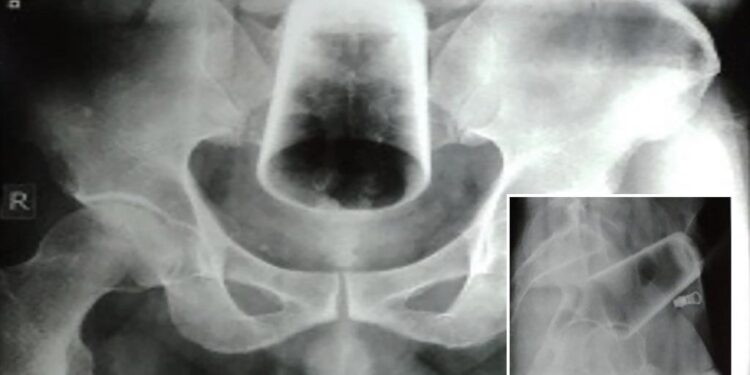

Αφού του έγινε μια ακτινογραφία, οι γιατροί προσπάθησαν να το αφαιρέσουν, αλλά δεν μπορούσαν να πιάσουν το γυαλί καθώς ήταν ανεστραμμένο.

Το ιατρικό προσωπικό πραγματοποίησε στη συνέχεια μια διερευνητική λαπαροτομία, η οποία είναι μια χειρουργική επέμβαση για να ανοίξει η κοιλιά. Σε εκείνο το σημείο, προσπάθησαν να μετακινήσουν το γυαλί έξω πιέζοντας το κατώτερο έντερο. «Επιχειρήθηκε να απομακρυνθεί το γυαλί μέσω του πρωκτού, αλλά αυτό ήταν ανεπιτυχές, καθώς το γυαλί βρισκόταν ψηλά», εξηγεί το περιοδικό Journal of Nepal Medical Centre. «Ως εκ τούτου, έγινε σιγμοειδής εντεροστομία και το γυαλί εξήχθη». Η εντεροστομία είναι η χειρουργική τομή σε ένα έντερο, η οποία επιτρέπει στους γιατρούς άμεση πρόσβαση στο γυαλί.